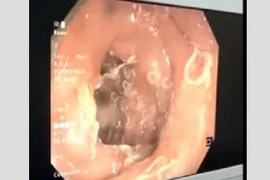

Người phụ nữ đến bệnh viện khám trong tình trạng đại tiện ra máu, qua nội soi dạ dày, tá tràng, bác sĩ phát hiện hàng trăm con giun móc “trú ngụ” thành tá tràng của người bệnh.